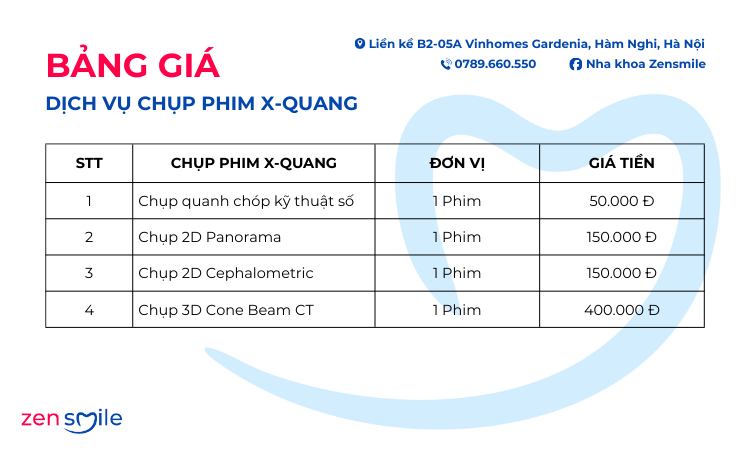

4. Bảng chi phí chụp phim X-quang tại Zensmile

Zensmile công khai chi phí minh bạch – không phát sinh. Miễn phí toàn bộ khi khách hàng sử dụng dịch vụ điều trị chuyên sâu tại Zensmile.

Chi phí các loại hình chụp X-quang răng tại Zensmile